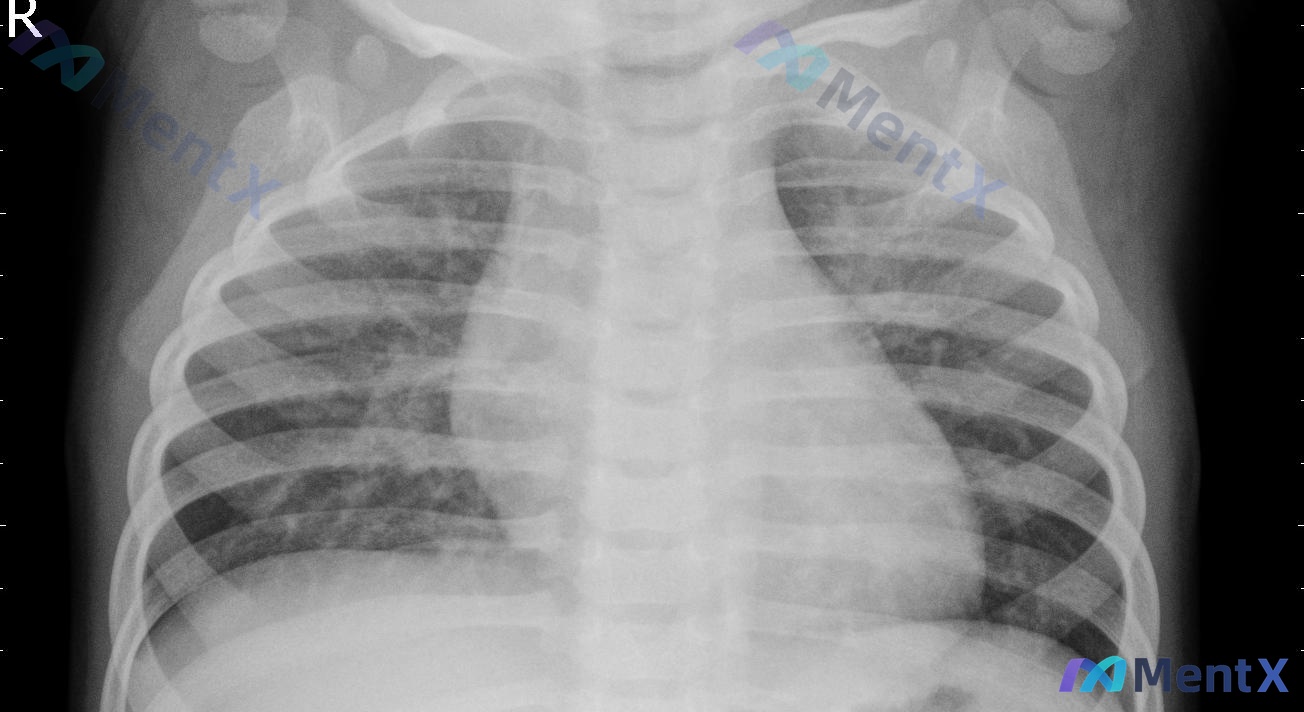

整理了一个儿科病例,题干和核心问题放出来,大家来捋一捋思路: 5岁女孩玩耍时吞下一颗弹珠,母亲诉患儿突发剧烈咳嗽伴异常呼吸声,几分钟后症状自行消失。 目前查体:脉搏100次/分,呼吸28次/分,一般情况尚可,右下肺野呼吸音减弱,可闻及轻微呼气性喘息。胸部X光检查可见右下叶下部1cm×1cm圆形异物影...